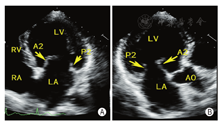

二尖瓣装置由前叶、后叶、腱索、乳头肌、瓣环和左室壁组成。两个瓣叶在前外交界和后内交界处相连接,均有相应的腱索和乳头肌。二尖瓣前叶和后叶分别可分成3个扇区,后叶天然的2个切迹将后叶分成3个部分,从前外交界向后内交界方向,依次为外侧叶P1、中间叶P2、内侧叶P3。前叶与之对应的区域依次为外侧叶A1、中间叶A2、内侧叶A3 (图1)。

通过采集以下切面显示二尖瓣瓣叶各扇区。①胸骨旁左室长轴切面:显示A2、P2(图5A);②二尖瓣水平短轴切面:显示整个前后叶(图5B);③心尖四腔心切面:显示A2、P2(图6A);④心尖长轴切面:显示A2、P2(图6B);⑤心尖二腔心切面:显示A1、P3(图7A);⑥心尖二尖瓣交界处长轴切面:显示P1、A2、P3(图7B)。

通过采集4个食管中段切面完整显示二尖瓣(图8)。①食管中段的四腔心切面:显示A2、A3和P1;②食管中段的二尖瓣交界处切面:显示A2、P1和P3;③食管中段的二腔心切面:显示A1、A2和P3;④食管中段的长轴切面:显示A2和P2。

MR介入治疗术前和术中,经常使用三维TEE的X-plane双切面(包括二尖瓣交界处二腔心切面及三腔心切面)来评估二尖瓣解剖:二尖瓣交界处二腔心切面能清晰显示二尖瓣后叶P1及P3、前叶A2,而三腔心切面能清晰显示二尖瓣前叶A2、后叶P2。也可通过二尖瓣的"三维外科视野"立体显示二尖瓣前后叶(图9)。